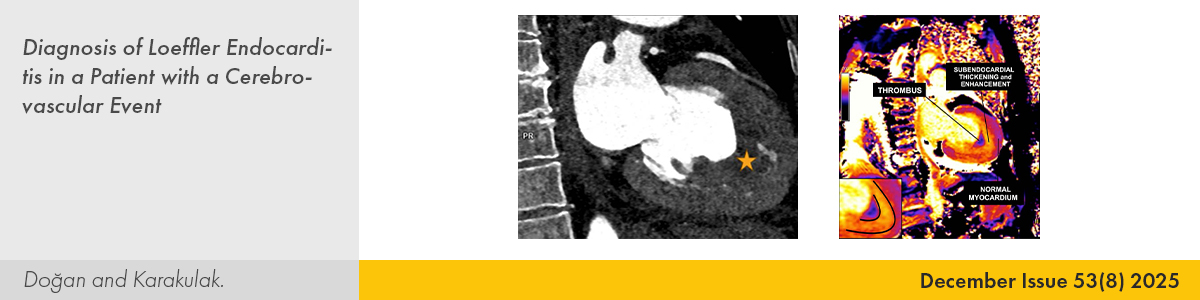

| CASE IMAGE | |